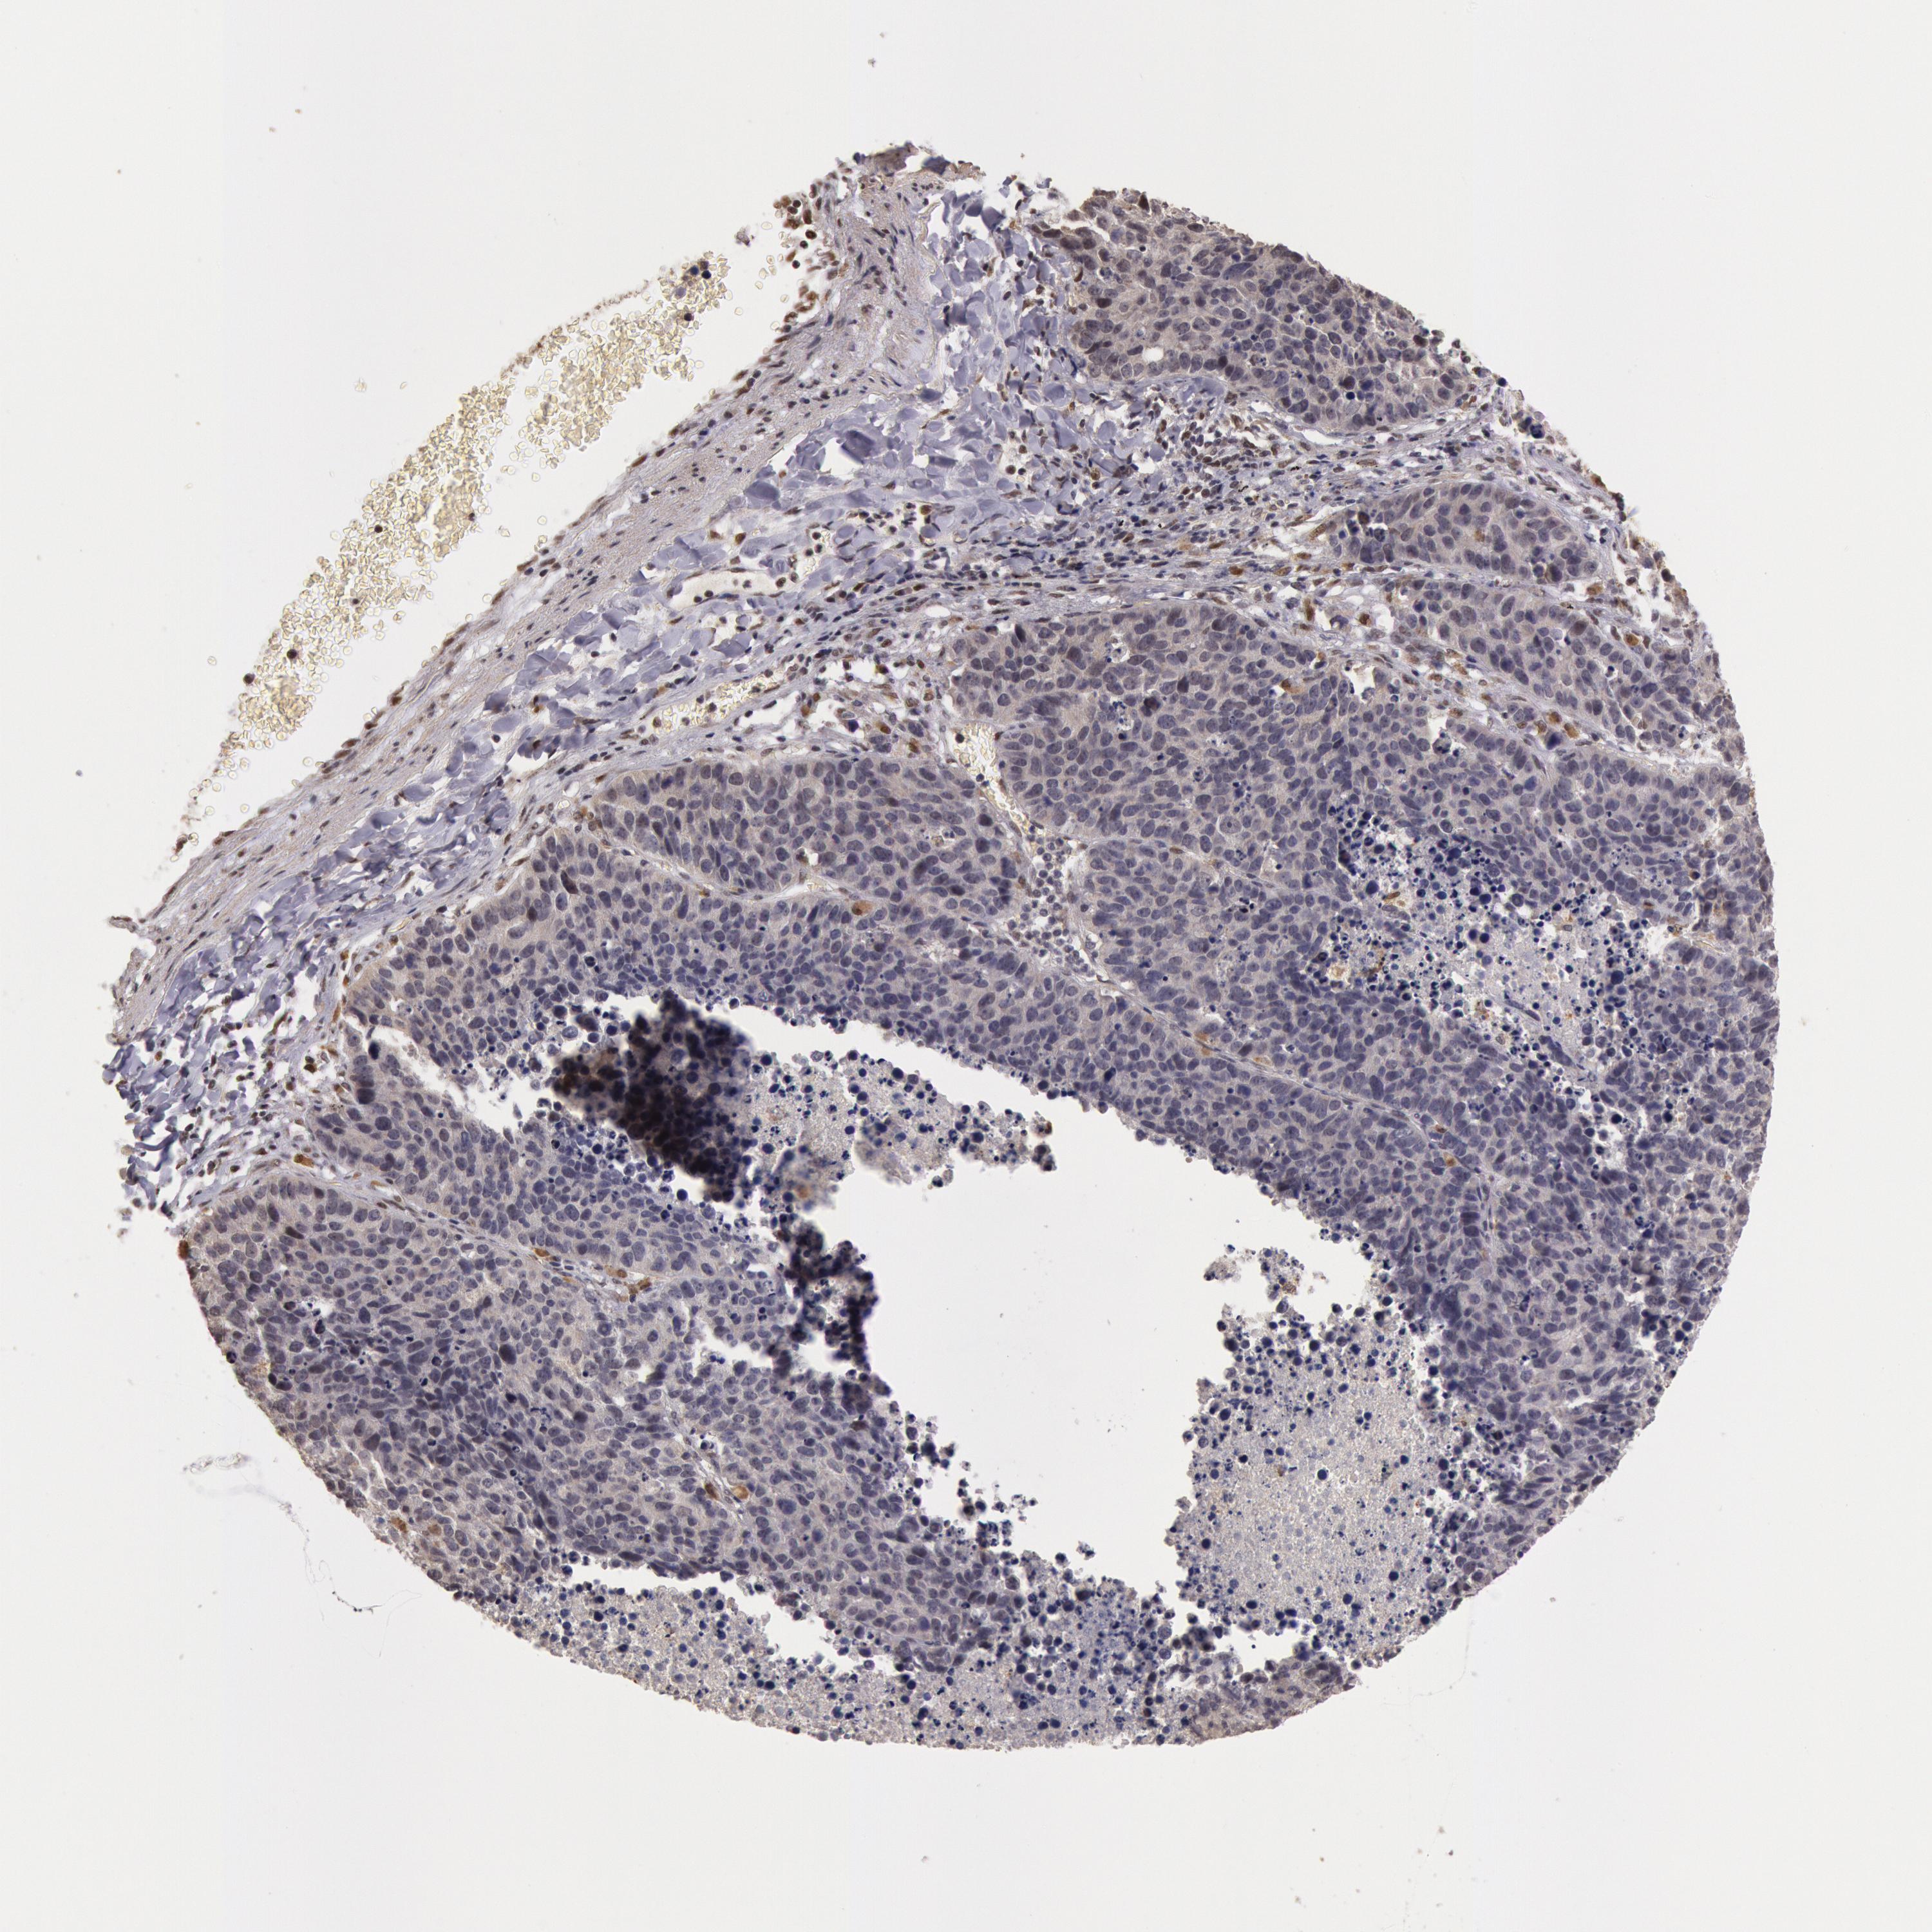

CANCER LUNG CANCER Show tissue menu

LUAD TCGA LUAD VALIDATION LUSC TCGA LUSC VALIDATION PROTEIN LUAD CPTAC PROTEIN LUSC CPTAC PROTEIN EXPRESSION

ANTIBODIES

AND

VALIDATION